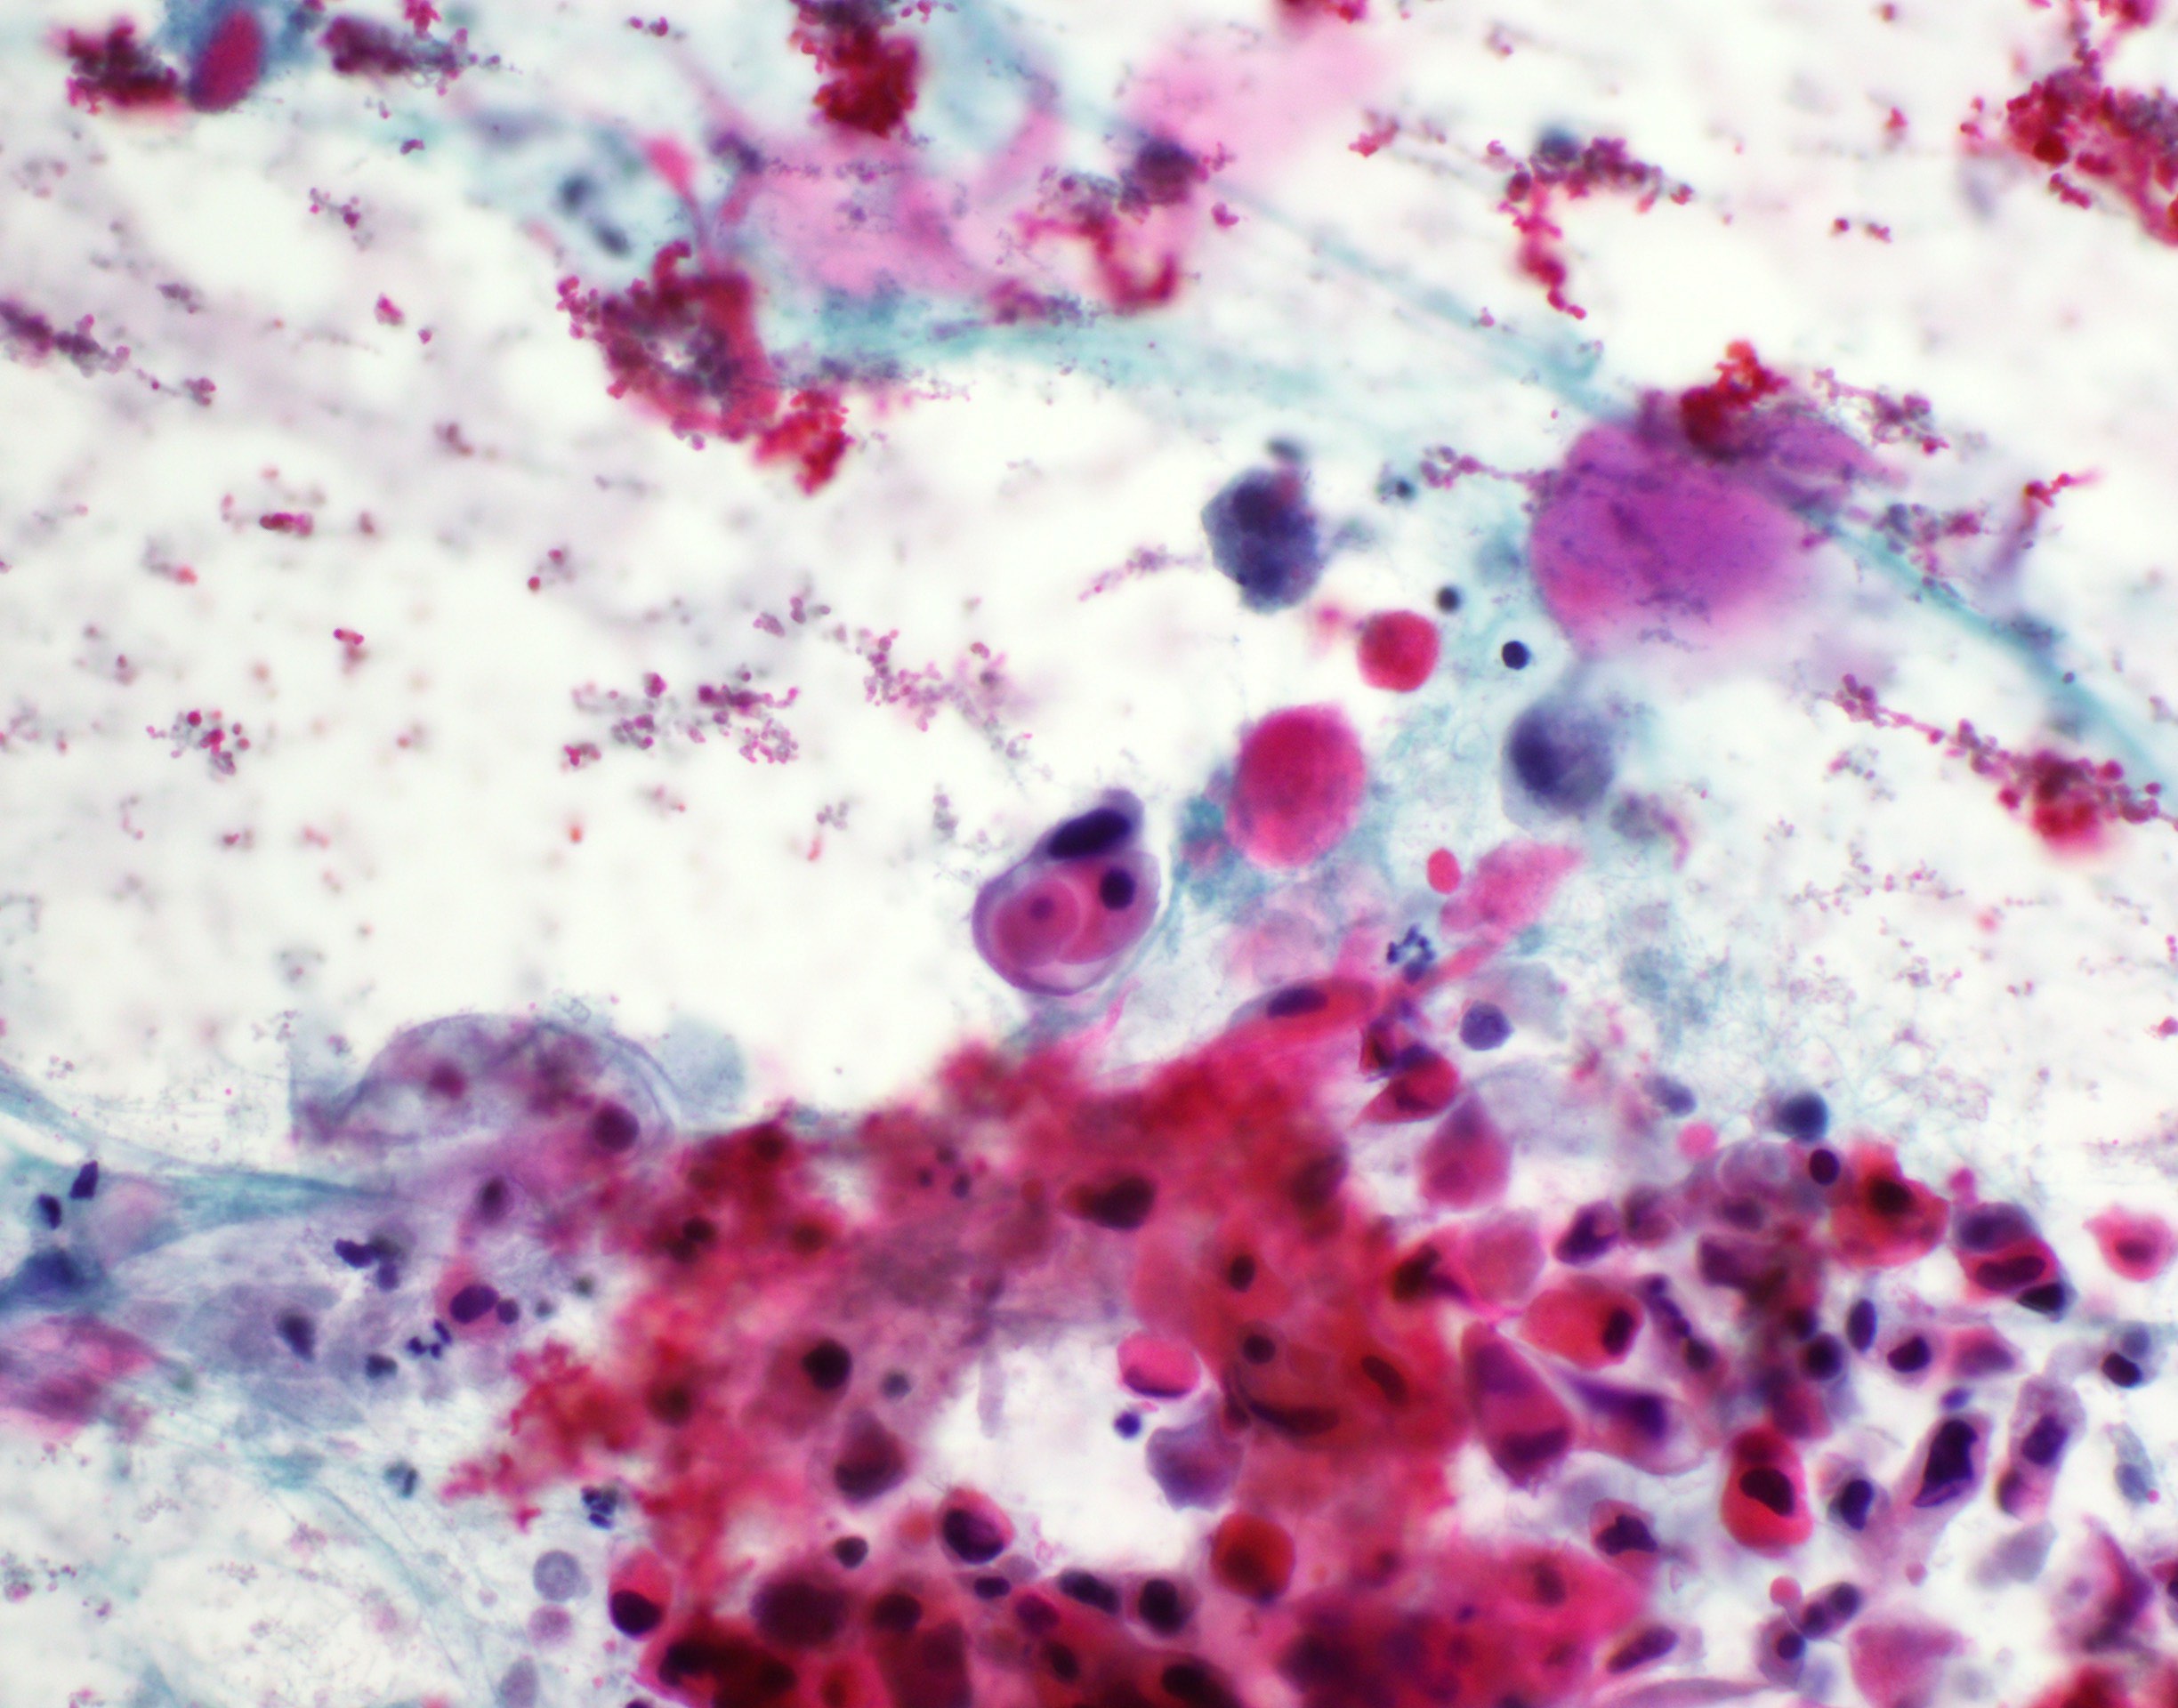

Cytology description

- Role of cytology only in investigation of regional or distant metastases

- Appearance depends on type and differentiation

- Conventional squamous cell carcinoma shows sheets and small clusters of large polygonal malignant cells with intercellular bridges and cytoplasmic or extracellular eosinophilic keratin

Cytology images